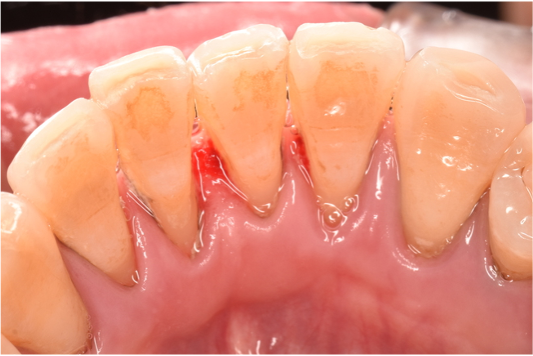

治療前

| カウンセリング・診断結果 | 下顎の前歯舌側に厚めの縁上歯石が付着していました。 |